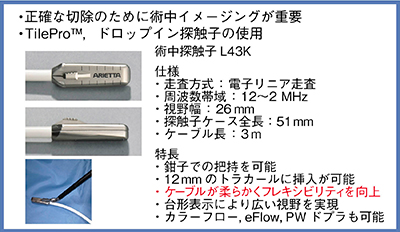

2.ドロップイン型プローブ「L43K」の有用性

そこで,当院でRAPNの導入に伴い使用を開始したのが,鉗子で把持可能なドロップイン型プローブのL43K(図1)である。L43KはLPN用のプローブよりも先端が小さく,ケーブルが柔らかいためフレキシビリティに優れるほか,腫瘍の輪郭に沿ってしっかり押し当てられるので,より良好な画像が得られるようになった。このため,より正確に腫瘍の切除ラインをイメージすることができる。そのイメージを基にしたロボットの繊細な操作が加わることで,きわめて精緻な手術が可能になると考えている。

図1 ドロップイン型の術中エコープローブL43K